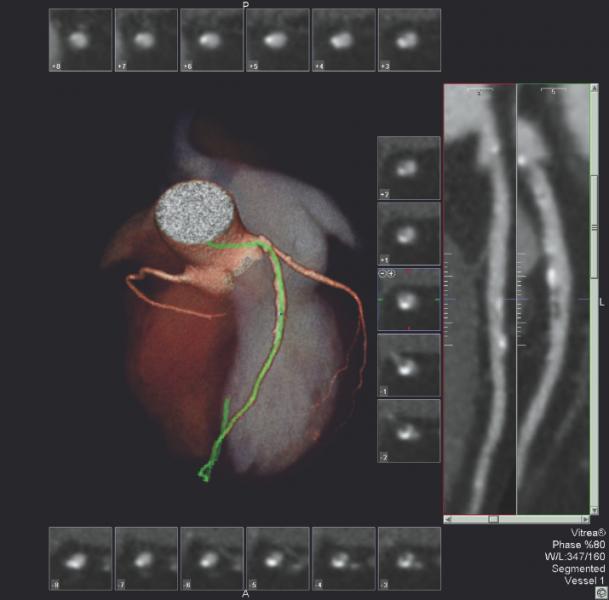

A CT myocardial perfusion image set showing perfusion defects in a color-coded iodine map and seen as darker areas of low contrast in the images below.

CT perfusion software works by mapping iodine contrast distributions in the myocardium throughout the cardiac cycle. These color-coded maps can be displayed as either bull's eye plots or overlaid on 3-D images of the heart, showing the wash in and wash out of contrast, which is used as a surrogate for blood. Areas of low contrast attenuation correlate with areas of low perfusion due to blocked arteries. Even without attenuation maps, many experienced cardiac CT readers can see shading defects in the myocardium caused by low areas of iodine contrast due to blockages.